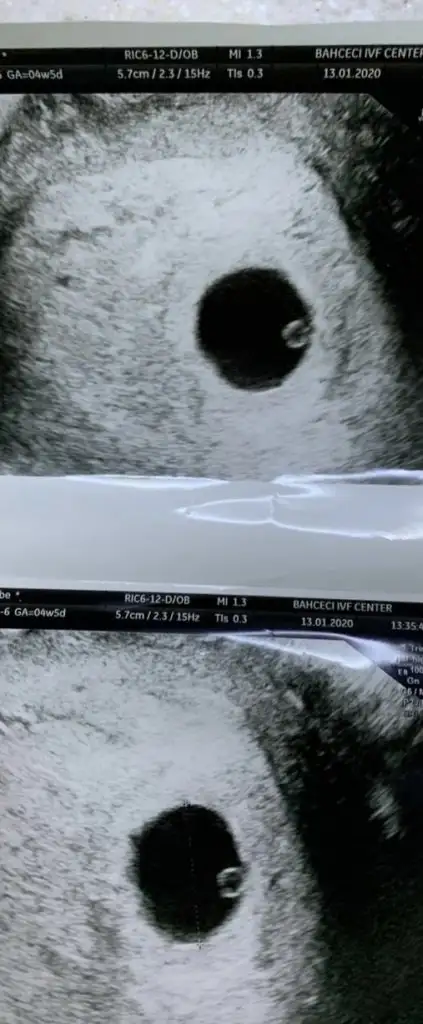

Ramzi Teorisi ve cinsiyet tahmini ( tutma olasılığı %85 miş )

Kızlar 6 yada 7 haftalık yorumlarmisiniz

Ikra meyra İlk resim 6 haftalık ikinci resim 10 haftalık cinsiyet tahmini yapacak varmı kızlar